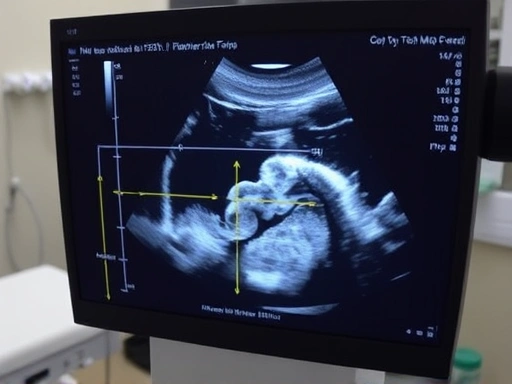

Close-up image of a pregnant woman receiving an ultrasound, focusing on the monitor displaying fetal growth measurements, with a concerned yet hopeful expression.

태아 발육부전은 주로 초음파 검사를 통해 진단합니다. 초음파 검사를 통해 태아의 크기, 양수 양, 혈류 등을 측정하여 태아의 성장 상태를 평가합니다.